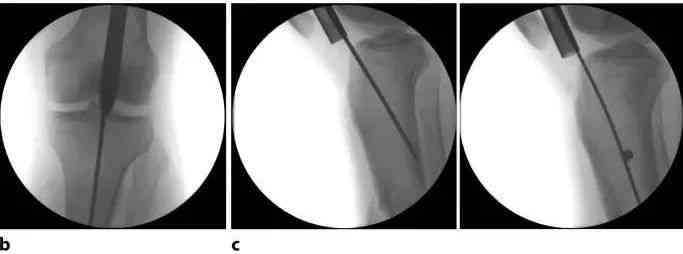

Paku blocking dipaké di wewengkon metaphyseal lega lamun guidewire atawa paku teu bisa dipuseurkeun paralel jeung sumbu longitudinal tulang atawa nalika narekahan misalignment dina hiji atawa duanana pesawat tetep dina mangsa sisipan paku.

Gambar 12b Gumantung kana lokasi narekahan jeung morfologi na, rupa-rupa parabot réduksi kayaning klip percutaneous, retractor, pelat sempalan leutik, sarta screws blocking bisa dipaké pikeun ngahontal alignment ditangtoskeun. Dina réduksi narekahan tibial proksimal, sok sanajan kalayan bantuan implants tambahan, saméméh muka kanal medullary ku pangeboran. Batang reaming diteruskeun sacara distal sareng diselapkeun kana tengah metafisis tibial distal. Saatos repositioning, panjang jeung diaméter paku ditangtukeun. Upami diperlukeun, ngagedekeun kanal tibial kana diaméter nu dipikahoyong ku reaming di increments 0,5 mm. Bukaan dina cecekelan leungeun baju pelindung ngamungkinkeun pikeun nyiram sareng nyeuseup lebu tina gabungan nalika reaming. Upami mungkin, disarankeun pikeun ngagunakeun paku kalayan diaméter minimum 10 mm. 5.0 mm Locking Bolt pikeun jenis paku ieu langkung tahan ka gagal tibatan 4.0 mm Locking Bolt anu dianggo pikeun paku anu langkung saé. Panjang kuku intramedullary biasana ditangtukeun ku pangawasa fluoroscopic.